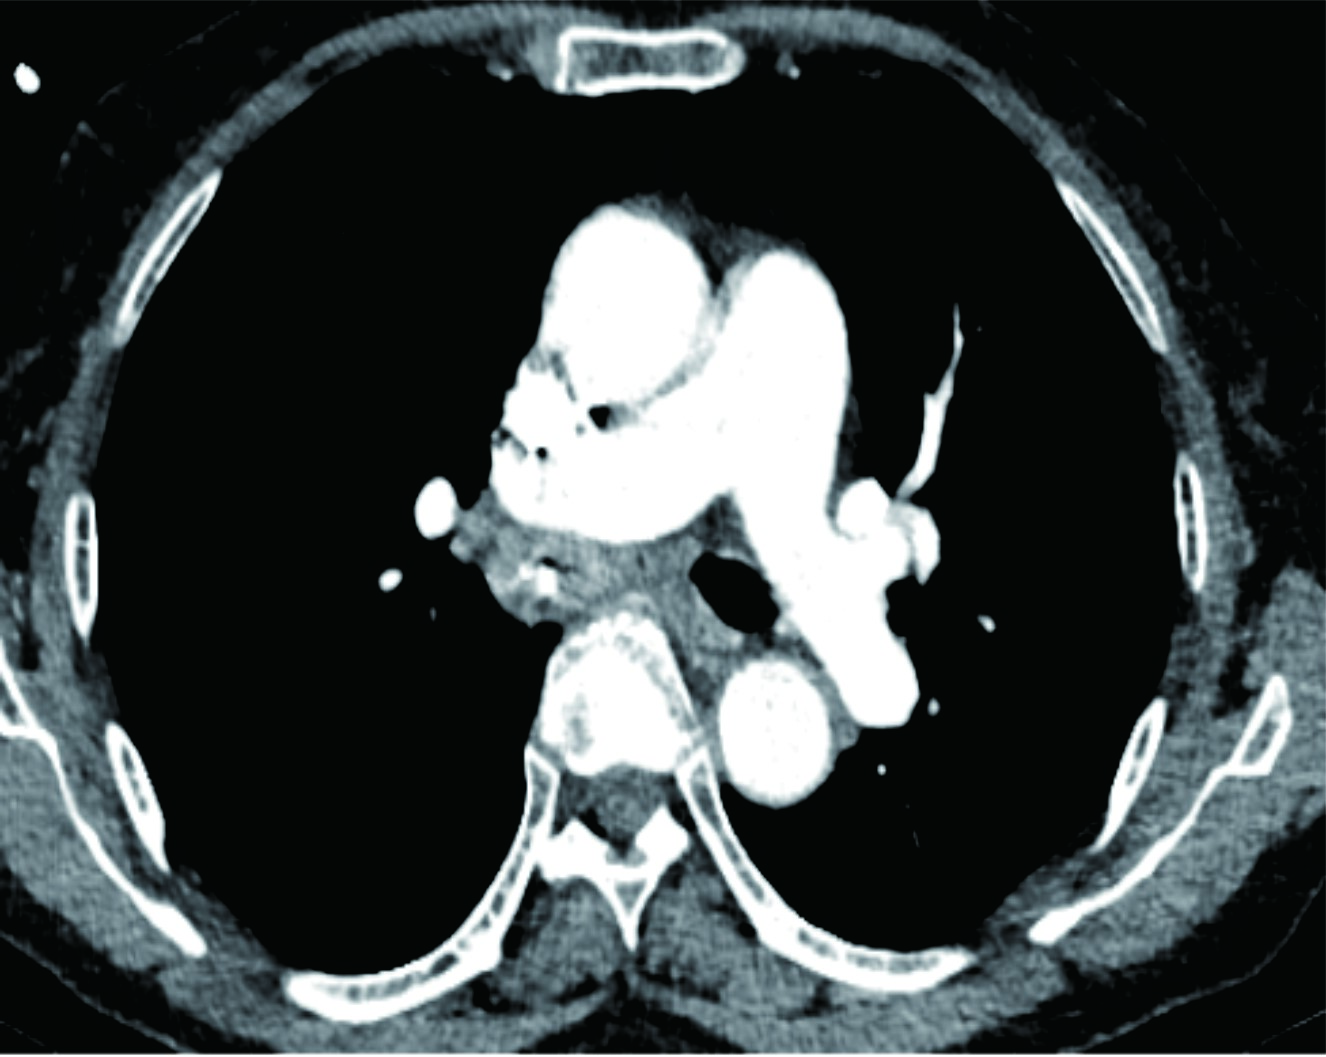

经科室详细安排,患者完成了胸部增强CT及电子支气管镜检查,结果让医生们大吃一惊:右侧主支气管内卡有一异物,异物周围肉芽组织显著增生,几乎将管腔完全堵塞,导致患者通气严重受阻。